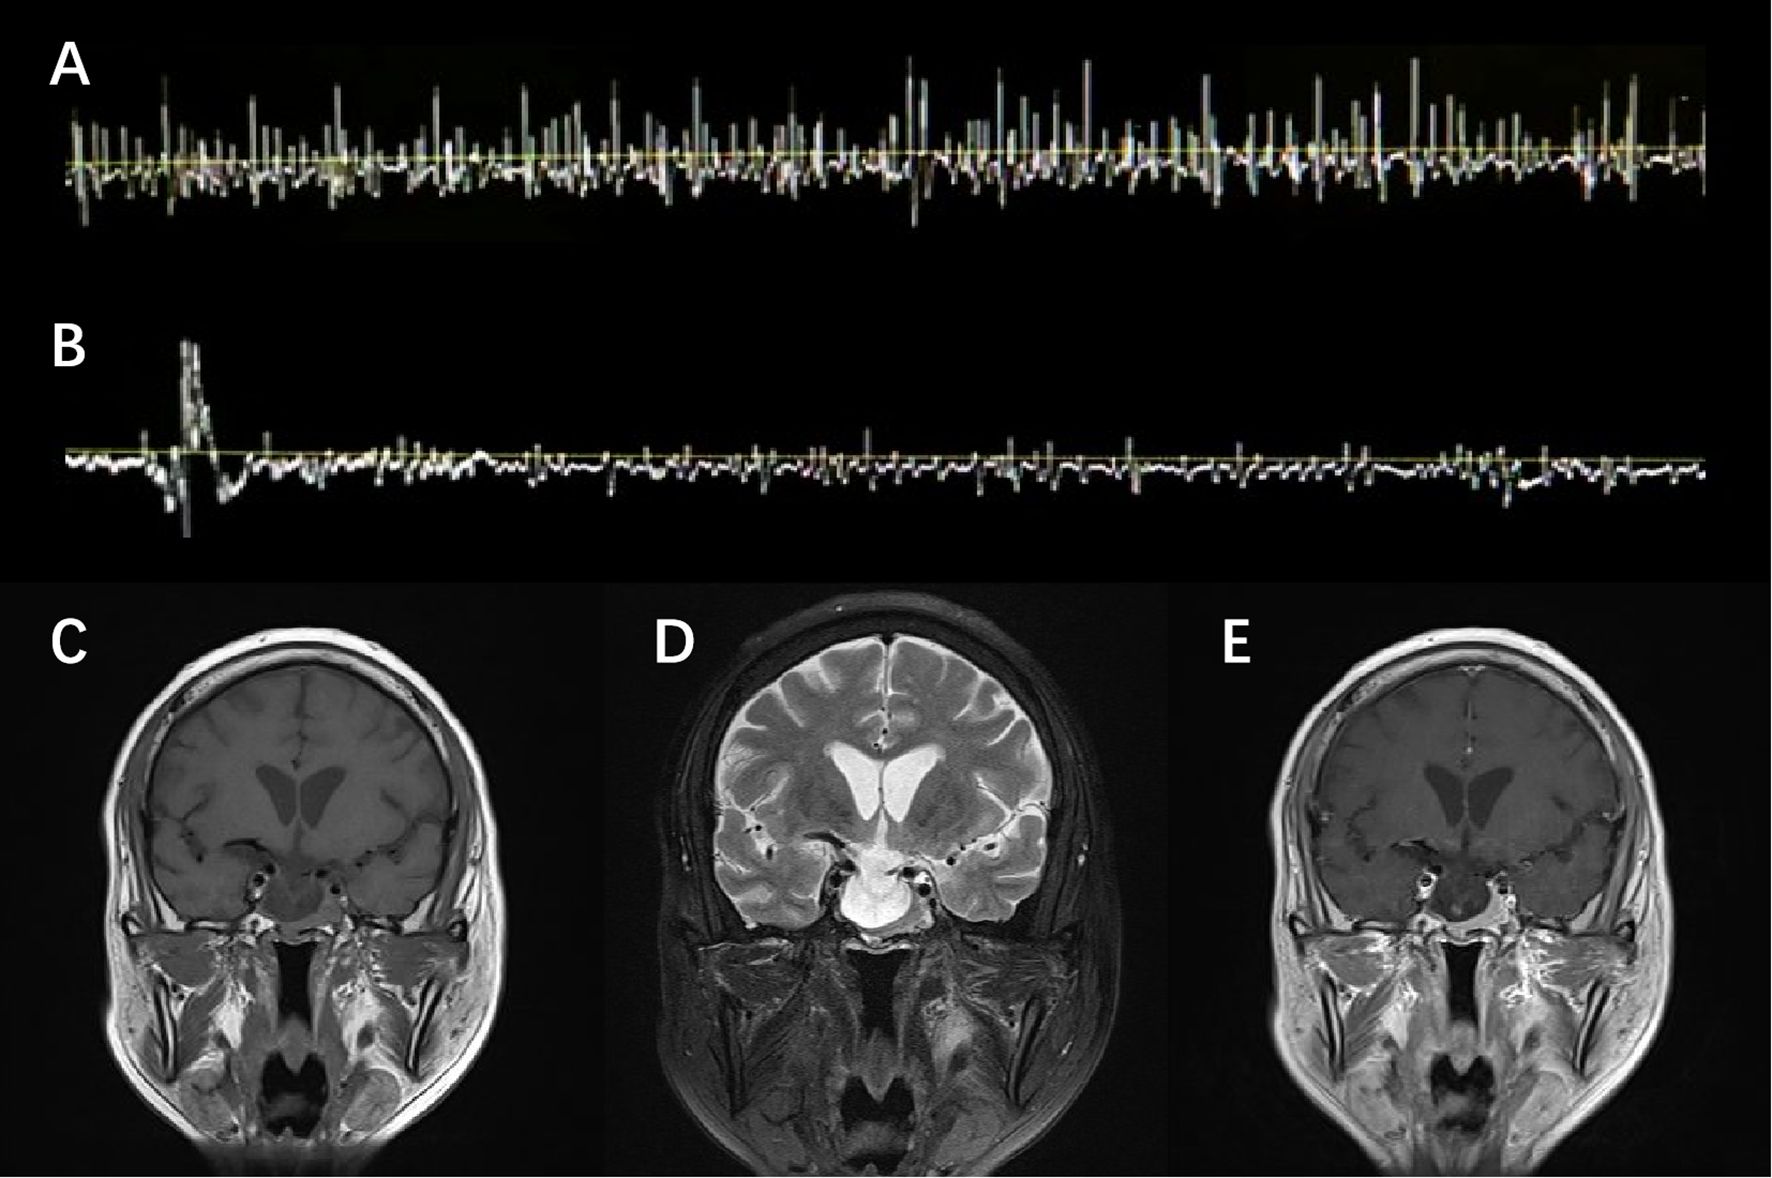

He was admitted with a suspected diagnosis of SPS and underwent relevant examinations. Laboratory tests were largely unremarkable except for inflammatory indicators and thyroid function panels, namely, an elevated erythrocyte sedimentation rate (ESR) of 33 mm/h, a borderline positive result of respiratory syncytial virus (RSV) IgM, and a decreased free thyroxine (FT4) level of 0.39 ng/dL (Supplementary Table). A lumbar puncture was performed, revealing cerebrospinal fluid (CSF) cell counts and a protein level of 4×106/L and 68.6 mg/dL, respectively. Despite an increased 24-h intrathecal IgG synthesis rate of 13.55 mg/24 h, the findings of type IV oligoclonal bands and a CSF serum albumin ratio of 9.46×10−3 indicated the breakdown of the blood–brain barrier and the absence of intrathecal IgG synthesis. No anti-GAD or anti-amphiphysin antibodies—both known to be pathogenic for SPS—were detected in either serum or CSF. EMG observed paroxysmal motor-unit potential firing of the right rectus abdominis at the resting state, which self-relieved after 4 min without using diazepam (Figures 1A,B). Clonazepam 1 mg daily was administered as standard SPS treatment, but no expected improvement in stiffness was observed. These atypical features raised red flags, promoting alternative explanations beside the diagnostic hypothesis of SPS.

Figure 1

Electromyographic (EMG) pattern and brain MRI images of the patient. The top row labeled A and B includes EMG observations, showing spontaneous motor-unit potential firing at the resting state, which self-relieved without diazepam. The bottom row labeled C, D, and E includes coronal brain MRI images, displaying a heterogeneously enhanced pituitary and empty sella.

Figure 1. EMG and MRI presentation. EMG observed spontaneous but transient motor-unit potential firing of the right rectus abdominis at the resting state (A), which self-relieved in 4 min without diazepam (B). T1-weighted (C), T2-weighted (D), and Gd-enhanced T1-weighted (E) MRI scan of the brain showed a heterogeneously enhanced pituitary and empty sella.

Though clonazepam was gradually withdrawn due to the side effects of drowsiness and feebleness, the symptoms persisted and rapidly progressed to somnolence and delirium. The electrolyte result reported a severe hyponatremia with a sodium level of 121 mmol/L. Standard intravenous and oral sodium supplementation was initiated, which proved ineffective in the subsequent 2 days. Further investigations were thus conducted. Brain magnetic resonance imaging (MRI) revealed a homogeneously enhanced pituitary with an empty sella, redirecting an alternative diagnosis to the underlying pituitary pathology (Figures 1C–E). A pituitary crisis was suspected based on an abnormal pituitary function panel (Supplementary Table), particularly disruption of gonadal function (FSH 0.97 mIU/mL, LH 0.38 mIU/mL, and PRL >204 ng/mL). Given the infection upon admission, the pituitary decompensation was presumably attributed to precipitated inflammatory stress. Meanwhile, the patient’s condition further deteriorated to the extent of developing acute coronary syndrome when the Troponin I level peaked at 4.636 ng/mL and the electrocardiogram showed ST-segment depression in the inferior and extensive anterior leads.